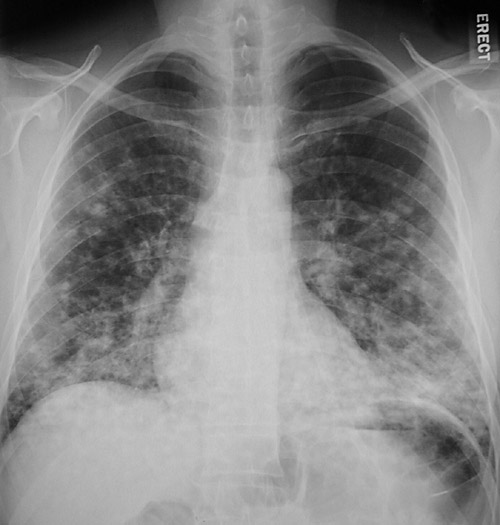

| The numerous irregular 0.5 to 1 cm nodular opacities seen here in a PA view above and lateral view below in the lung are more prominent posteriorly and inferiorly. This patient proved to have bronchiolitis obliterans with organizing pneumonia (BOOP). |